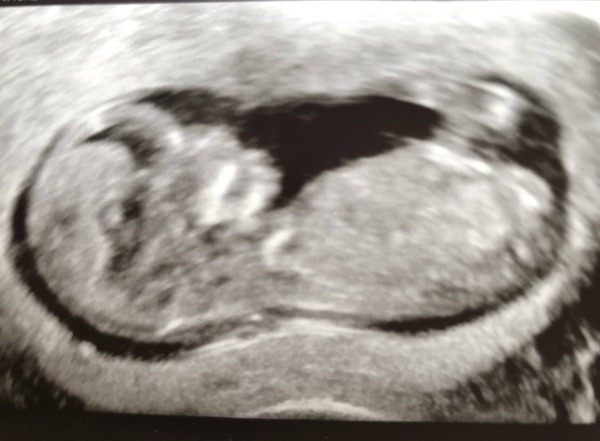

Evening everyone! I think some of you might be on the ‘autumn girls’ FB group so may already know as I updated there earlier - but my scan went really well today! Had to have an internal to get measurements (turns out I have a tilted womb and anterior placenta) but baby is measuring 1 day ahead and all looks normal!! It was so amazing and we are so relieved. Thanks for all your support so far! Xxx

@ahuss I thought I was dead on 12 weeks today but baby is measuring 12+1! Such a relief to be measuring slightly ahead, as with my first loss I was measuring behind at an early scan and then miscarried a few weeks later.

@Cafeaulait27 congratulations on your scan and a lovely pictures...cutie!!

@cafeaulait27 what a beautiful scan! You must be so thrilled to see your healthy baby in there!